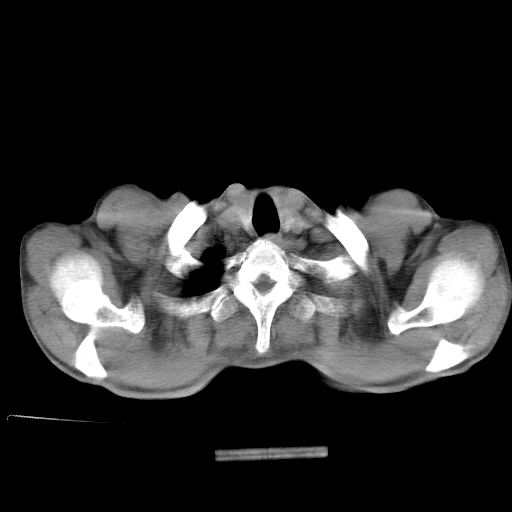

以下是引用杀毒软件在2009-4-28 17:58:00的发言:[br]考虑----左肺慢性肺脓肿形成继发上叶含气不良---抗炎后复查---待排肿瘤所致[br][br][本贴已被 杀毒软件 于 2009-4-28 18:01:26 修改过]